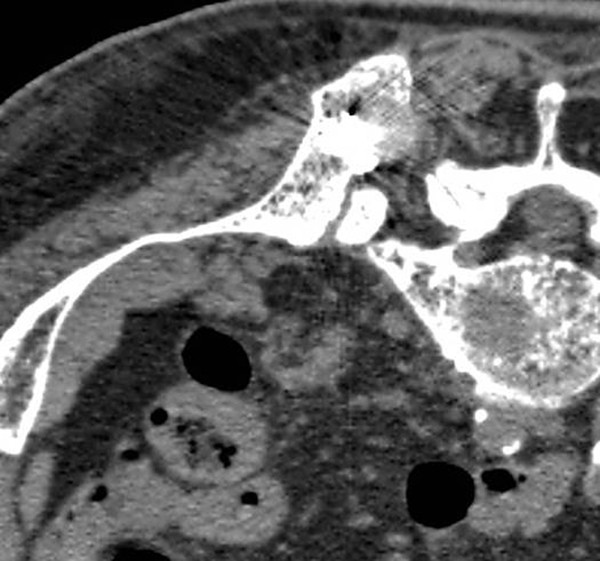

Метастазы костных тканей